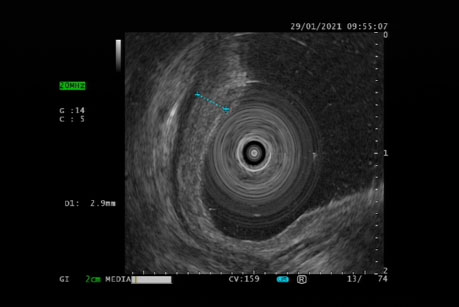

超声内镜观察病变的浸润深度